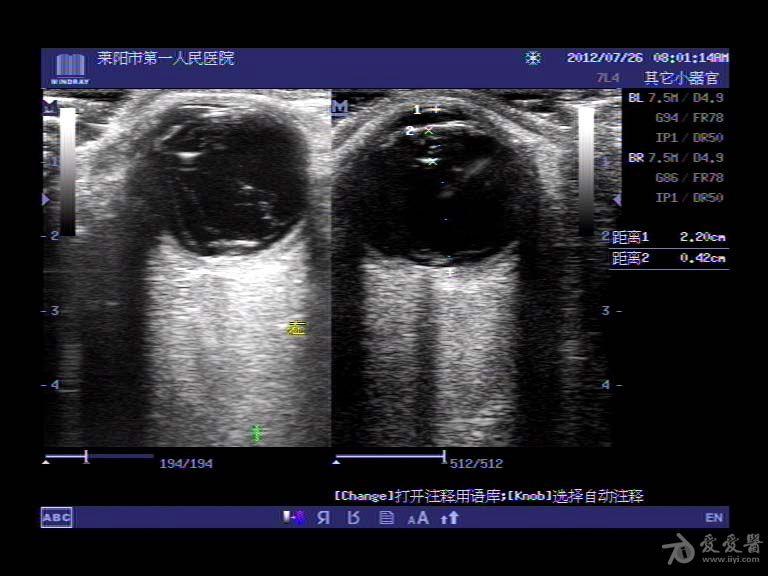

- 是网脱,脉脱还是玻璃体后脱离? - 超声医学讨论版 - 爱爱医医学论坛图片尺寸768x576